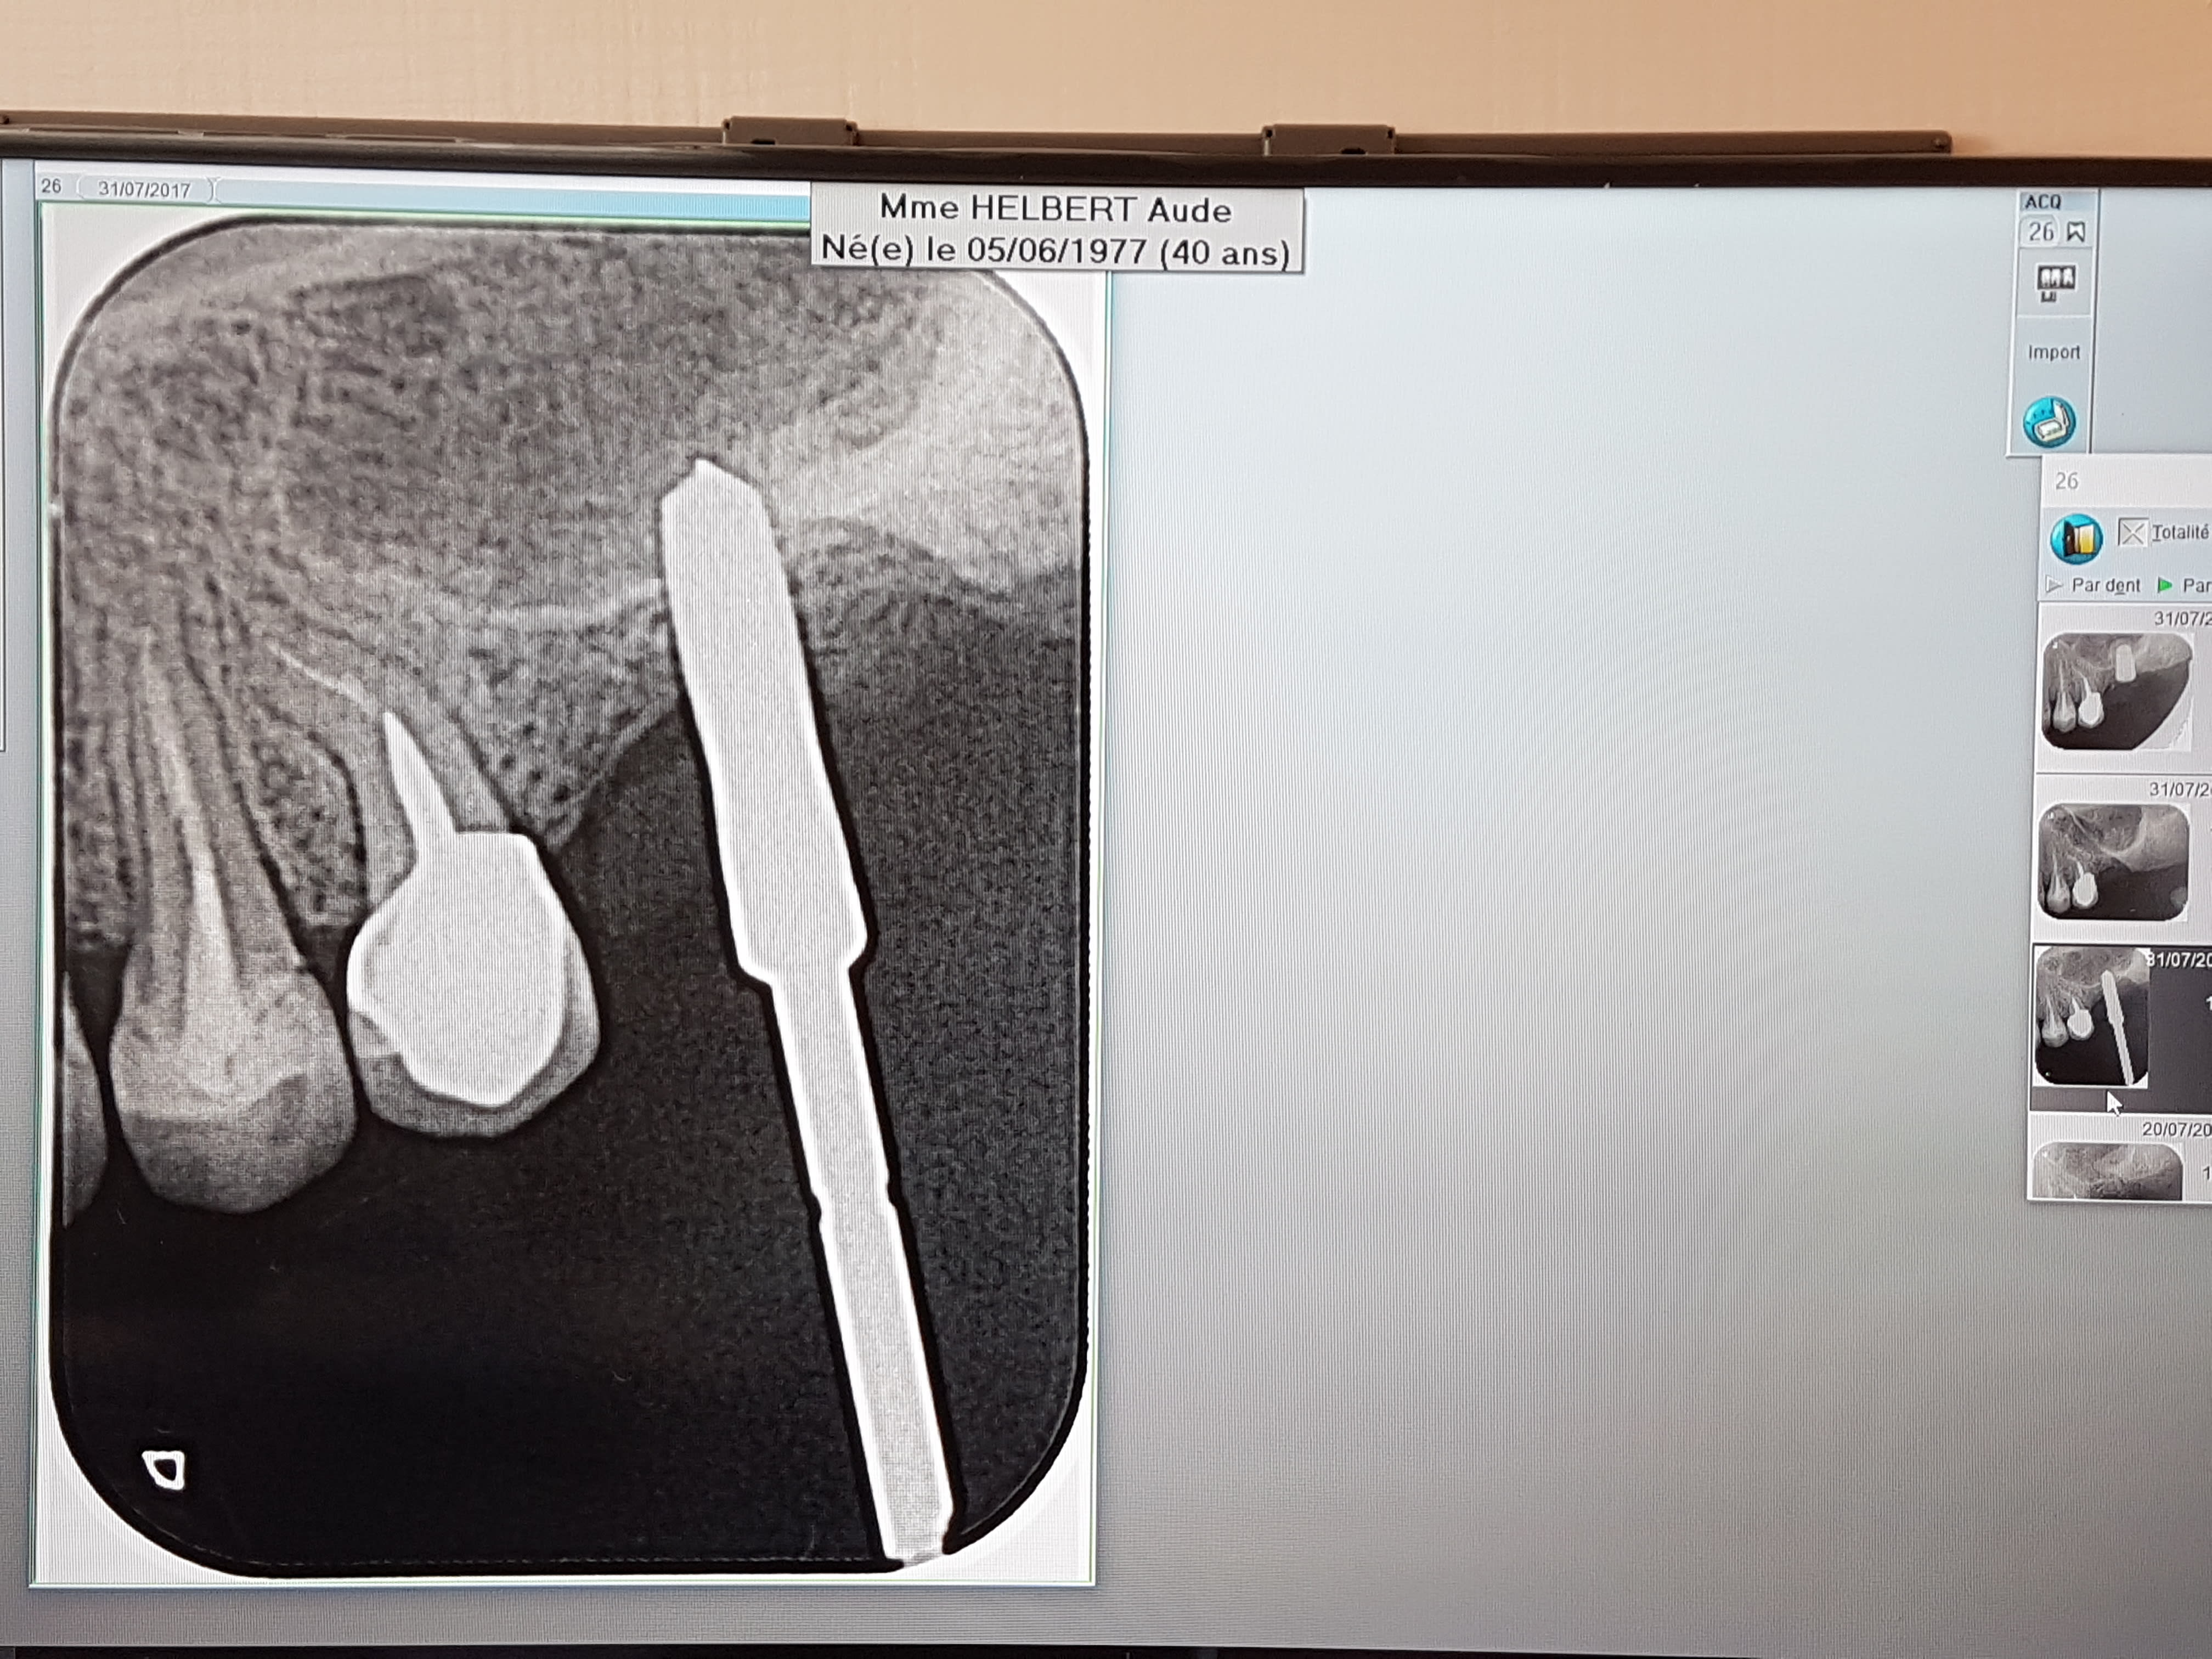

Un autre exemple de l'utilisation des versah. Cas d'EII sur 26, Forage dans le septum et osseodensification. Souleve' de sinus de 5mm mais sans comblement. Controle à 7 jours, aucune douleur post op.

20171018 094131 hjcxwj - Eugenol

20171018 094139 iocwui - Eugenol

20171018 095402 zrdzxf - Eugenol